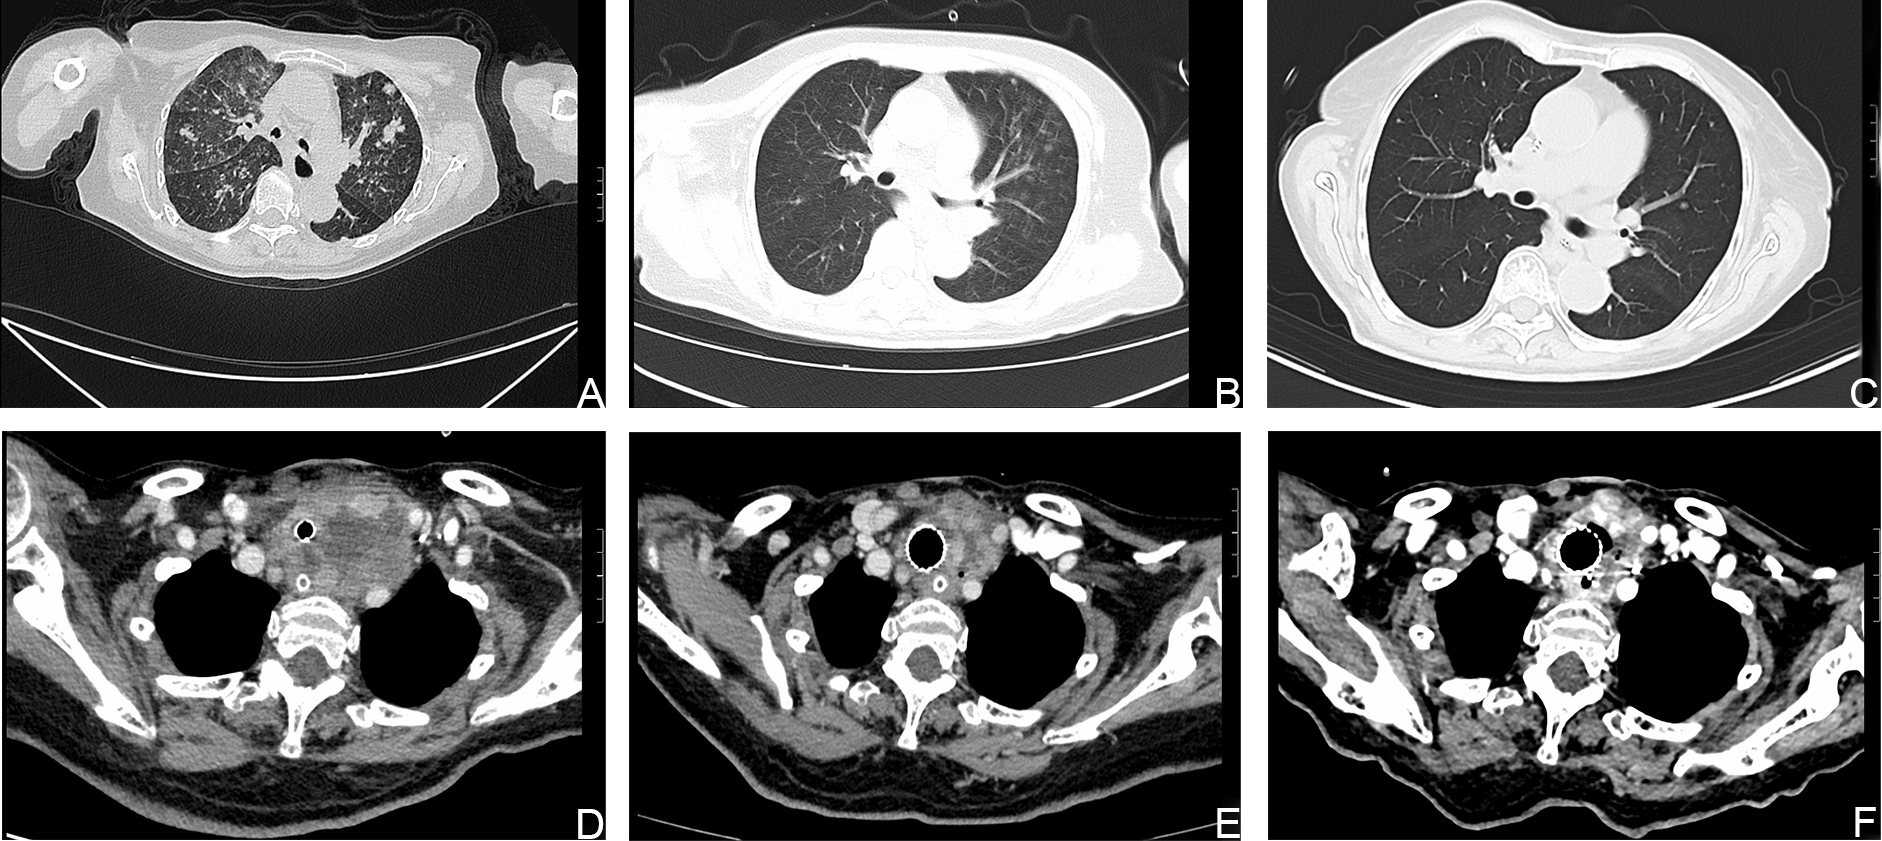

A 73-year-old woman presented to the emergency department of West China Hospital, Sichuan University, on January 31, 2022, because of a neck mass with chest and airway tightness. Previously, FNA was performed at her local hospital, and the results showed metastatic, poorly differentiated squamous cell carcinoma. Upon arrival in the emergency room, the patient suddenly lost consciousness. The emergency physicians immediately diagnosed respiratory failure and intubated the patient. To comprehensively evaluate the condition of patient, CT was performed and showed that there was a mass (6.3×5.6 cm) located in the left lobe region of the thyroid gland, which wrapped and invaded the trachea and esophagus, both of which were compressed to varying degrees, resulting in stenosis. Nodules of varying size were scattered throughout both lungs, with the largest nodule measuring 1.8 cm in diameter, which we suspect to be metastatic lesions (Figure 3). The laboratory examination upon admission revealed the following: FT3 2.08 pmol/L (reference range, 3.60–7.50 pmol/L), FT4 9.39 pmol/L (reference range, 12.0–22.0 pmol/L), TRAb 2.79 IU/l (reference range, <1.75 IU/l), WBC 12.99×10/L (reference range, 3.5–9.5 10^9/L), Hb 99 g/L (115–150 g/L), and PLT 259×10/L (100–300 10^9/L); TSH, hTg, TGAb, and CEA were unremarkable. She had a 13-year history of papillary thyroid cancer (PTC) and had previously undergone total thyroidectomy, double central lymph node dissection, plus left cervical lymph node dissection in our hospital. Levothyroxine 75 µg in parallel with radioactive iodine [(131)I] therapy three times, were administered in after the operation. There was no personal or hereditary family history of cardiovascular or cerebrovascular disease. An appointment was set with a thyroid surgeon from our institution on the same day. After the completely treating the infection that emerged in the patient’s lungs during the consultation on February 7, 2022, she was admitted to the Thyroid and Parathyroid Surgery Center. A covered stent was used instead of tracheal intubation with the assistance of the Department of Otorhinolaryngology. Due to the patient was critically ill after admission and had obvious symptoms of neck compression. In an effort to strive for treatment time, while the patient underwent US-FNA, we communicated with the family and obtained the consent to empirically administer treatment with dabrafenib and trametinib (given the close similarity to that of case 1), and the final pathological results and genetic testing also confirmed the effectiveness of our medication. We selected a mass in the left lobe region of the thyroid gland by ultrasonographic localization, punctured the fine-needle into the interior of the nodule and multipoint aspiration was performed under the monitoring of ultrasound. Histological examination was performed postoperatively on fixed specimens with alcohol. Immunohistochemical analyses showed tissue positivity for the following markers: HBME-1, CK19, G-3, BRAF-VE, PCK, and PAX8. In addition, TERT promoter mutation (C288T) were identified by Molecular testing in the mass. Combined the morphology and all of the above findings led to a diagnosis of PTC with a mutation at position 228 of the TERT gene promoter (Figure 4). Under receiving comprehensive treatment from the nutrition, infection, and respiratory departments, the patient’s condition improved after 5 days of dabrafenib and trametinib, and her symptoms of dyspnea, dysphagia, and hoarseness disappeared. Unexpectedly, she was required dose reductions of dabrafenib and adds radiotherapy because of edema of both lower extremities with petechiae. Three months later, the patient developed a tracheoesophageal fistula, which improved after conservative treatment. After ∼8 months of treatment, numerous metastatic lesions had lessened on computed tomography. The survival time of the patient has reached 10 months since she diagnosis of PTC. At present, the patient is in a state of no recurrence and metastasis, and there is no obvious adverse reaction after taking dabrafenib and trametinib.

Figure 3

Computed tomography (CT) images showing that the size of the lesions had decreased. (A, D). CT images of the metastatic lesions in the lung and neck respectively, before treatment with dabrafenib and trametinib. (B, C, E, F). CT images of the metastatic lesions after treatment with dabrafenib and trametinib.